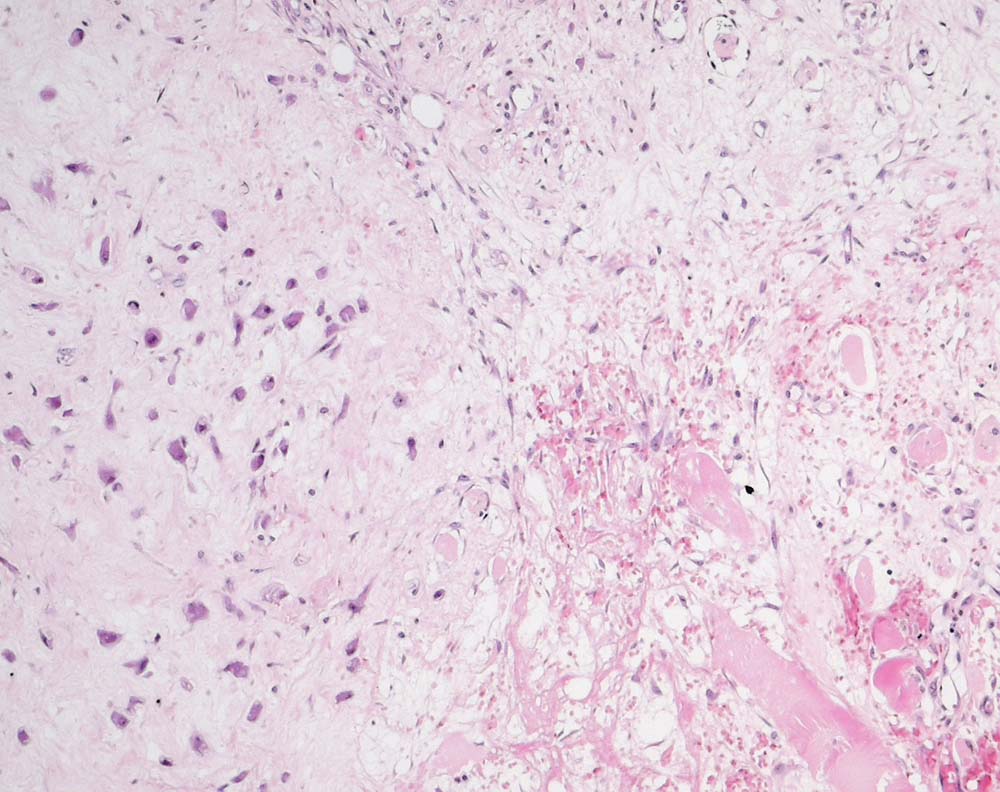

Proliferative Myositis

Rechts unten im Bild sind einzelne residuelle Skelettmuskelfasern zu sehen. Diese sind eingebettet in eine lockere Fibrose mit Erythrozytenextravasaten, plumpen Fibroblasten und Myofibroblasten. Links im Bild sind zahlreiche ganglionartige Riesenzellen sichtbar.

Tumor der Muskulatur am rechten Oberschenkel.

Histologie

100